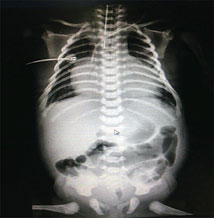

A su ingreso a UCIN con facies características de síndrome de Down y síndrome de dificultad respiratoria que ameritó progresión a fase III de ventilación. A nivel hemodinámico precordio hiperdinámico, ruidos cardiacos arrítmicos, desdoblamiento del segundo ruido, frecuencia cardiaca de 65 lpm. Se realizó electrocardiograma y radiografía (figuras 1 y 2).